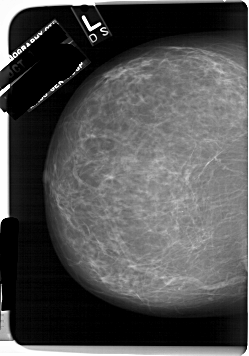

A_1232_1.LEFT_MLO

LEFT_MLO LINES 6661 PIXELS_PER_LINE 4966 BITS_PER_PIXEL 12 RESOLUTION 43.5 NON_OVERLAY